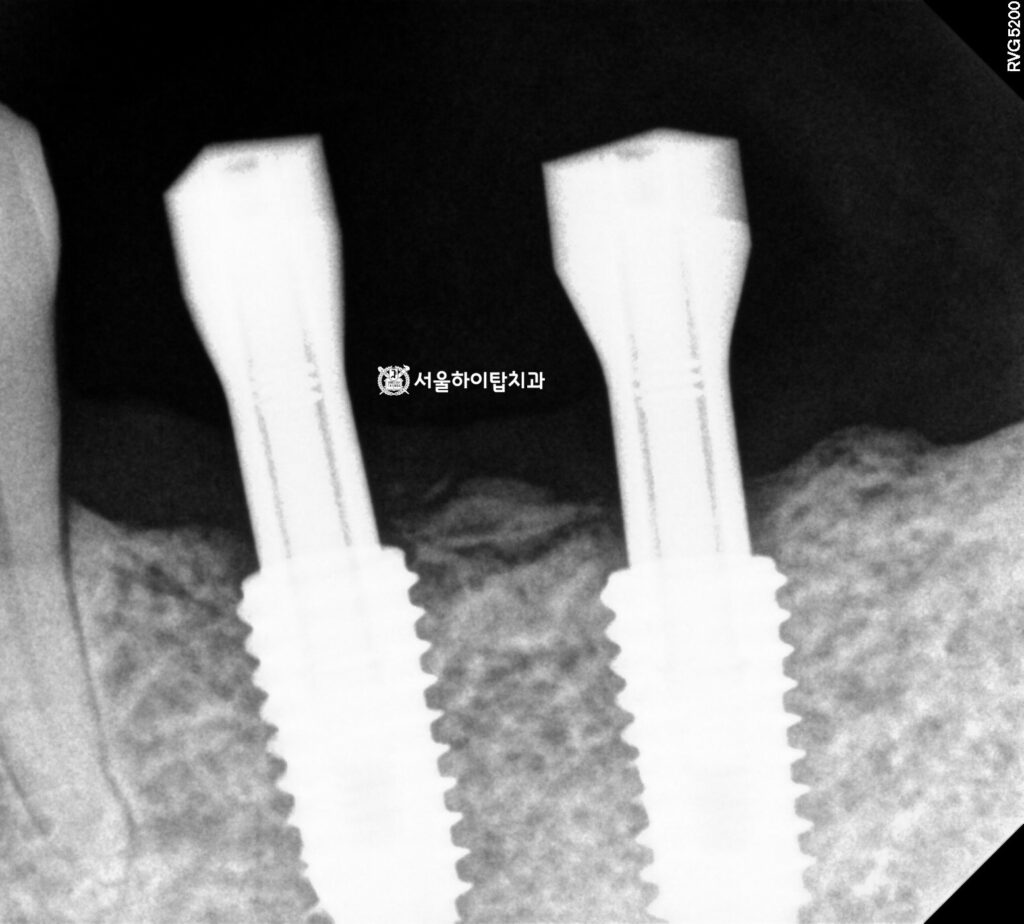

3. 수술 완료

위 시뮬레이션을 통해

예측된 위치에 식립된

모습입니다.

4. 최종 결과

골 융합이 충분히 이루어졌으며,

지르코니아 크라운으로 제작되면서

기능과 심미 모두 만족스러운 결과를

얻은 것으로 보여집니다.